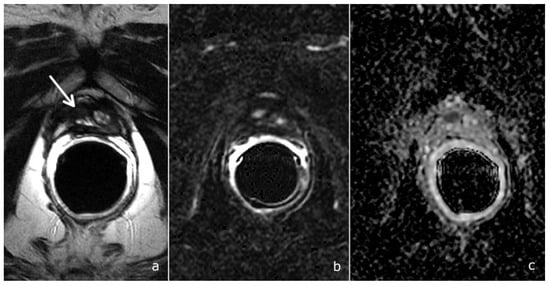

- Diffusion-weighted imaging (DWI): a single-shot echo-planar sequence with a high b-value (2000 s/mm2) and another single-shot echo-planar sequence with two different b-values (50 and 1000 s/mm2), this latter for the calculation of the apparent diffusion coefficient (ADC) map.

- DCE acquisition: three-dimensional (3D) T1-weighted Time-of-Flight Spoiled Gradient-Recalled sequence on the axial plane during the intravenous injection of a gadolinium-based contrast agent at a flow rate of 3 mL/sec followed by 15 mL of saline solution. The 3D data sets were acquired with a 10 s temporal resolution; the acquisitions before the contrast agent administration were analyzed to detect foci of hemorrhage.

- Scores of 1 and 2 were assigned to lesions with a very low and low likelihood of recurrence

- Score 3 was assigned if the presence of recurrence was uncertain

- Scores 4 and 5 were assigned when the likelihood of recurrence was high and very high